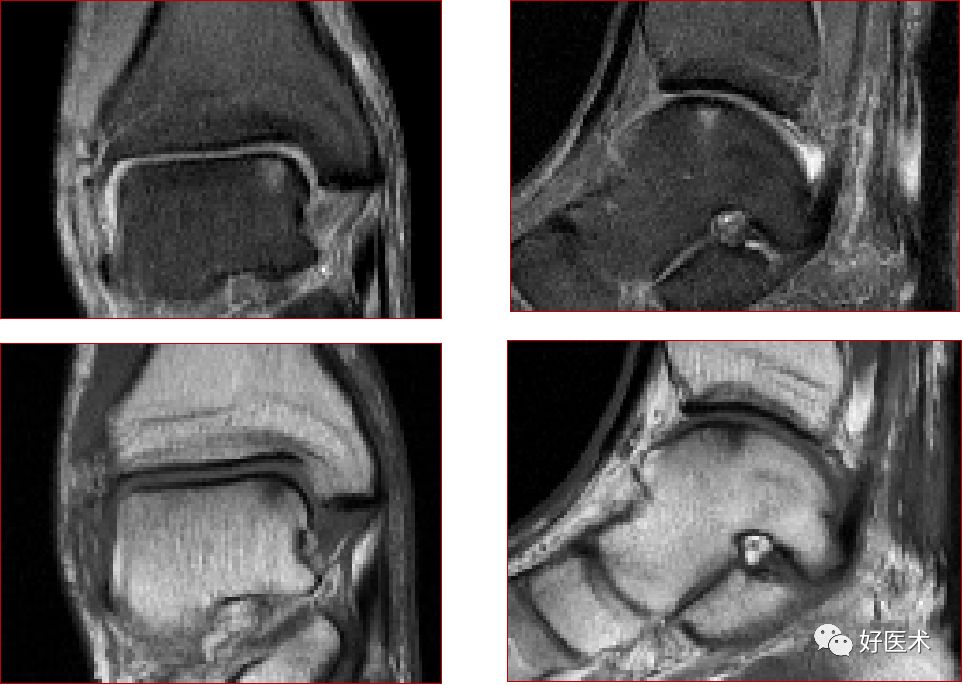

三、骨软骨病变

距骨骨软骨损伤,好发于前外侧、后内侧,尤其是后内侧,与内外翻损伤相关。

距骨骨软骨损伤分级